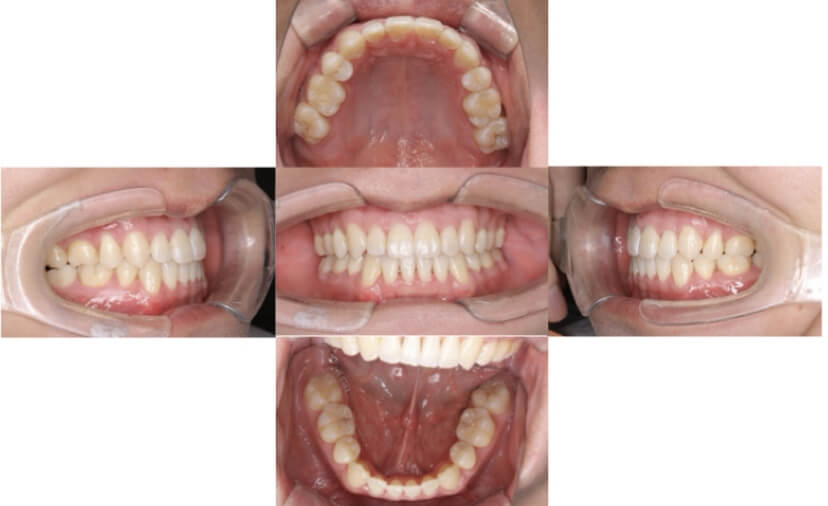

AFTER

症例2

上下顎前突、叢生

抜歯

ブラケット矯正

症例解説

上下顎前突、叢生(上下出っ歯、上下の前歯のガタガタ)のケースです。

装置はラビアル(上下表側)で、上下顎の小臼歯を4本抜歯を行っています。抜歯したスペースを使って、上下の前歯の後方移動と叢生(ガタガタ)の改善を行っています。